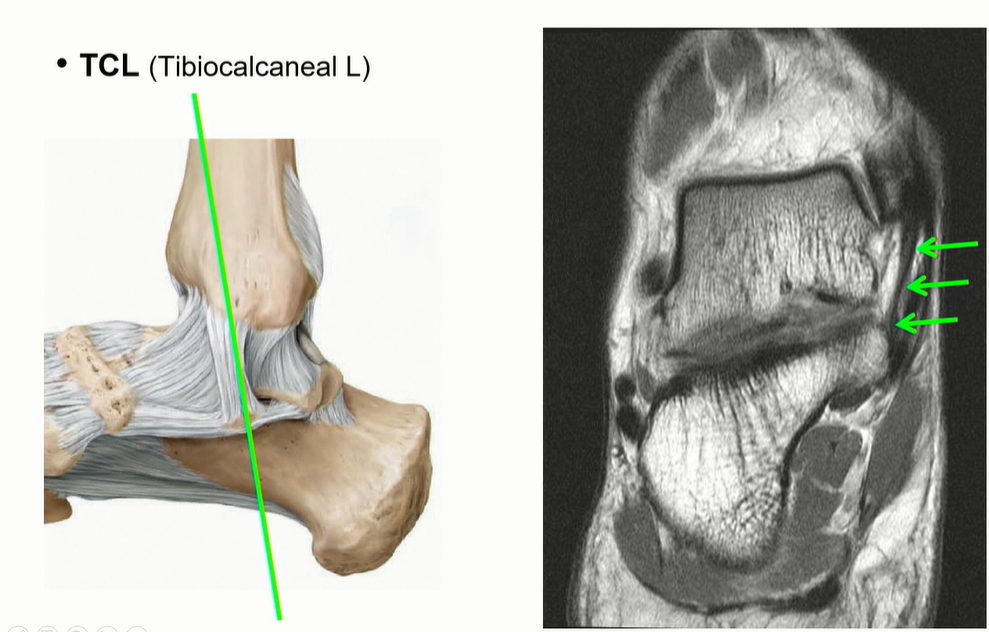

Tibiocalcaneal ligament는 calcaneus의 sustentaculum tali로 이어짐. 비교적 수직으로 주행하기 때문에 관찰 용이.

(Deltoid ligament의 superficial ligament의 3번에 해당)